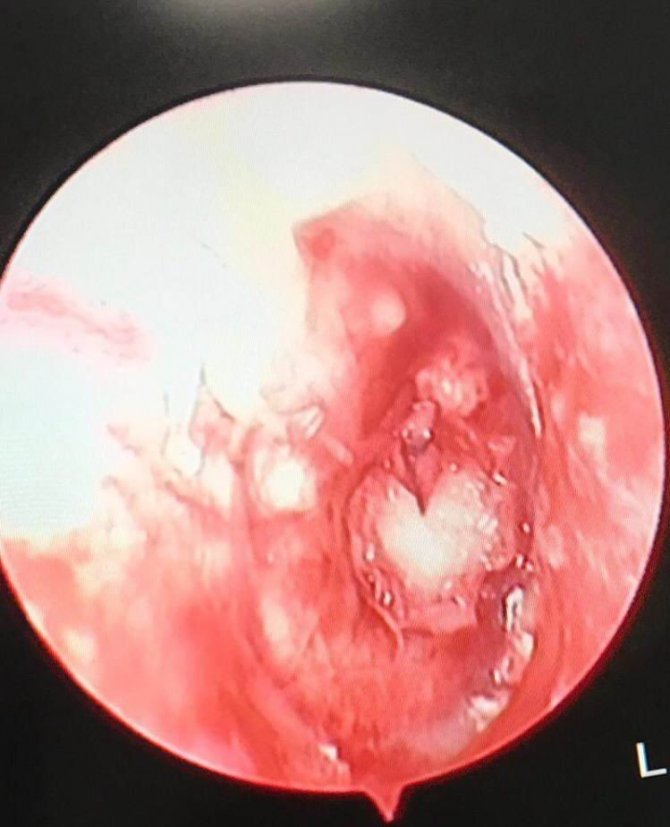

Manisa’nın Salihli ilçesinde yaşayan 21 yaşındaki gencin kulağındaki delik, özel bir hastanede görevli Kulak Burun Boğaz Uzmanı Op. Dr. Selcan Kesgin tarafından uygulanan Endoskopik Timpanoplasti ameliyatıyla onarıldı. Uygulanan Endoskopik Timpanoplasti ameliyatının ise Salihli’de ilk kez yapıldığı öğrenildi.

Salihli’de yaşayan 21 yaşındaki Serhat Demir, kulak zarındaki delik, çocukluğundan beri işitme azlığı ve iltihaplı kulak akıntısı sebebiyle ilçedeki özel bir hastaneye başvurdu. Hastanenin Kulak Burun Boğan Uzmanı Op. Dr. Selcan Kesgin tarafından yapılan muayene ve sonrasında yapılan tetkiklerinde Demir’in her iki kulak zarında delik olduğu ve buna bağlı olarak sık kulak enfeksiyonu ve işitme azlığı belirlendi. Hasta, Op. Dr. Kesgin tarafından Endoskopik Timpanoplasti ameliyatına alındı. Demir, gerçekleştirilen başarılı bir ameliyat ile kulağındaki delik onarıldı ve sağlığına kavuştu.

Başarılı operasyonu gerçekleştiren Op. Dr. Kesgin, bu şekilde yapılan kulak ameliyatının Salihli’de bir ilk olma özelliği taşıdığını söyledi. Kulak arkasından ya da önünden kesi olmaksızın özel endoskoplar vasıtasıyla kulak kanalı içerisinden operasyonu gerçekleştirdiklerini belirten Op. Dr. Kesgin “Hastaya kliniğimizde başarılı bir şekilde Endoskopik Endomeatal Kronik Otit Cerrahisi gerçekleştirildi. Bu şekilde yapılan kulak ameliyatının ilçemiz de ve hastanemizde ilk olma özelliği taşıyor” dedi.